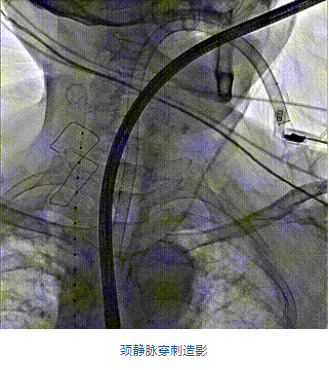

2022年5月27日,四川大學(xué)華西醫(yī)院心臟內(nèi)科陳茂、馮沅教授帶領(lǐng)的瓣膜病介入治療多學(xué)科團隊,在國內(nèi)首次采用純介入方式通過穿刺右側(cè)頸靜脈成功完成經(jīng)導(dǎo)管三尖瓣置換。植入的人工瓣膜是具有中國自主知識產(chǎn)權(quán)的LuX-Valve Plus系統(tǒng)。術(shù)中上海長海醫(yī)院陸方林教授和喬帆副教授給予了在線支持。

團隊前期經(jīng)過多次討論,制定了周密的手術(shù)策略和預(yù)案。由于患者已是近九旬的超高齡老人,傳統(tǒng)外科開胸手術(shù)風(fēng)險極高,純介入經(jīng)血管三尖瓣替換能夠明顯減少創(chuàng)傷。術(shù)中陳茂及馮沅教授結(jié)合體表定位在造影指示下精準(zhǔn)穿刺右側(cè)頸靜脈并預(yù)置兩把血管縫合器。成功建立經(jīng)皮血管入路后在食道超聲和DSA的引導(dǎo)下順利完成人工瓣膜植入,術(shù)后超聲和造影顯示人工三尖瓣同軸性良好,瓣架固定牢靠,無反流和瓣周漏,平均跨瓣壓差降為1mmHg。術(shù)畢收緊預(yù)置的血管縫合器縫線完成止血,縫合效果滿意,在手術(shù)室即刻拔除氣管插管。